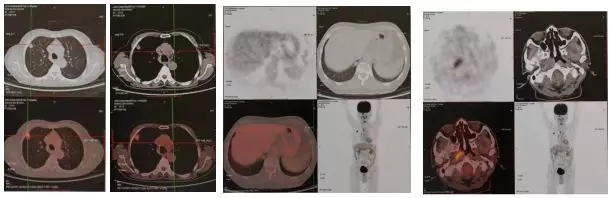

患者于2017年6月到某医院行PET-CT检查,显示除肺内散在病灶外,在患者的右侧鼻咽部发现,咽隐窝消失,鼻咽侧壁黏膜增厚,出现一个高代谢的病灶。当时的PET-CT的诊断是:右肺上叶结节SUVmax5.8,考虑周围型肺癌;双肺结节FDG无代谢,不除外肺转移;右侧鼻咽部高代谢灶SUVmax4.7,延迟后SUVmax6.2不除外恶性;右侧咽旁及颈部小淋巴结,代谢稍增高,待除外转移。

图二:2017.7.6PET-CT检查结果

患者在PET-CT检查后,行鼻咽镜检查,病理结果:(右侧鼻咽部)低分化侵润性鳞状细胞癌。